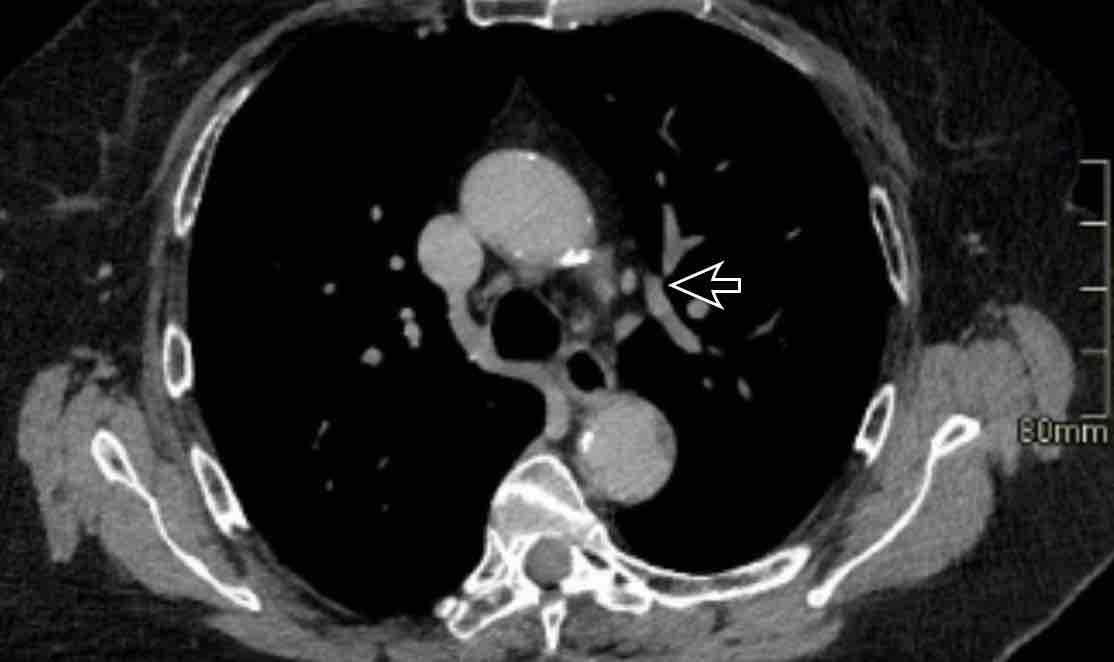

Hình ảnh

Huyết khối bám thành trung tâm ở bệnh nhân bị bệnh huyết khối tắc mạch mạn tính kèm giãn buồng tim phải, phù hợp với tăng áp động mạch phổi do huyết khối tắc mạch mạn tính (CTEPH).